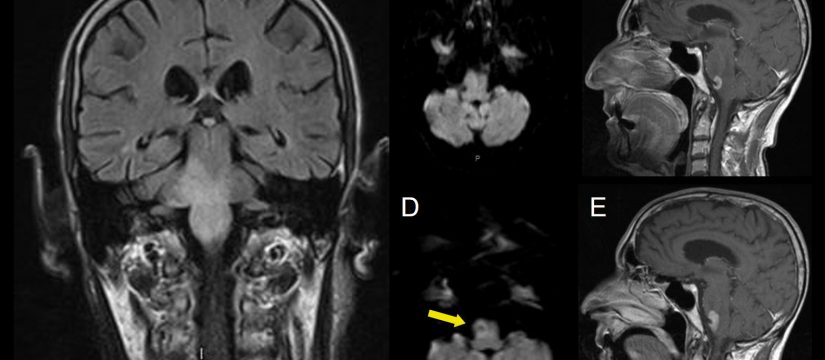

Varón de 40 años con esclerosis múltiple remitente-recurrente ya conocida, que consulta por disartria de varios días de evolución.